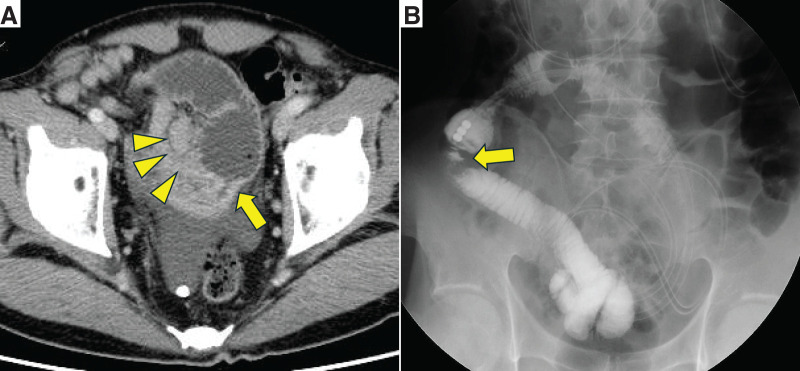

Introduction: Primary gastrointestinal follicular lymphoma (FL) rarely causes intestinal stricture. We report two cases of small intestinal FL presenting with stricture.

Case presentation: Case 1: A 63-year-old man presented with small intestinal obstruction. CT demonstrated ileal wall thickening and enlarged lymph nodes. Partial ileal resection confirmed primary ileal FL, immunohistochemically positive for CD10, CD20, and BCL-2. Case 2: A 79-year-old woman with a 7-year history of jejunal strictures underwent right hemicolectomy for ascending colon cancer and partial jejunal resection. Pathologic examination showed concurrent jejunal FL and colon adenocarcinoma. Immunohistochemical findings were the same as in Case 1. In both patients, postoperative positron-emission tomography-CT showed no residual lymphoma. Both were monitored clinically without chemotherapy.